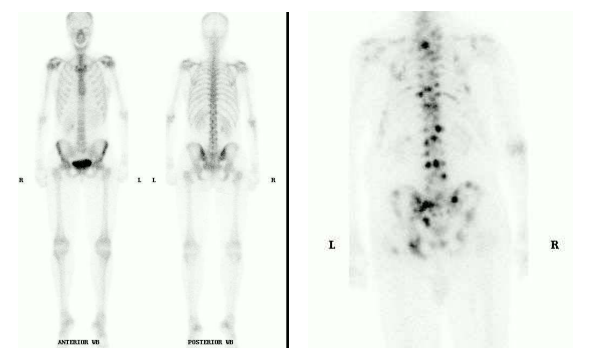

Bone scan

Principles, Indications, and Examples

Principles and indications

Detection, staging and follow-up of bone metastasis

Differentiating between osteomyelitis and cellulitis

Determination of bone viability

Evaluation of difficult fracture (stress fracture, fracture in battered child)

Evaluation of prosthetic joint problems (loosening, infected prosthesis)

Evaluation of bone pain in patient with normal plain radiograph (unexplained bone pain) Radiotracer: 99mTc-MDP (methylene diphosphonate)

Pathophysiology

Chemisorption to the hydroxyapatite crystal

Increased uptake

Increased blood flow

Increased osteoid formation

Increased mineralization of osteoid

Interrupted sympathetic nerve supply